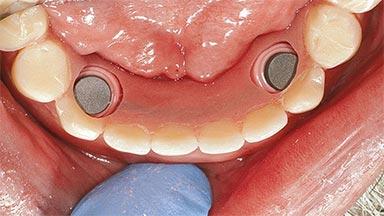

An 83-year-old man presented together with his caregiver at the dental department of the Medical University of Innsbruck, Austria with complaints of swelling in the right maxillary canine area and loss of retention of his 5-years-old mandibular denture. The patient had a significant medical history (20 years) of bipolar affective disorder with moderate depression (F 31.3) and dementia in Alzheimer’s disease (F 00.2). The patient had been in ambulant psychiatric therapy for his depressive illness for the past 20 years. He lived alone and had no children; his sister assisted with daily living. She reported that the patient exhibited compulsive hoarding behavior. In the previous two months, she had noted increasing disorientation and vertigo in the patient. She therefore accompanied him for a medical consultation at the Department of Psychiatry and Psychotherapy of the Medical University of Innsbruck. He was released home after a 6-week inpatient stay.

# of Implants 2

Type of Implants One-Piece

Attachment One-Piece

Prosthesis Type RDP

Defining Characteristics Fully edentulous lower jaw to be rehabilitated with an implant-borne removable overdenture